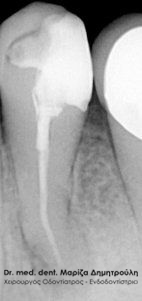

Στο συγκεκριμένο περιστατικό η μορφολογία της ρίζας παρουσιάζει ιδιαίτερο ενδιαφέρον, καθώς η ρίζα έχει τη μορφή τελικού “S”. Απουσιάζει η αρχική ακτινογραφία του δοντιού. Η απονεύρωση διεκπεραιώθηκε χωρίς να θιγεί η ανατομία της ρίζας του δοντιού.